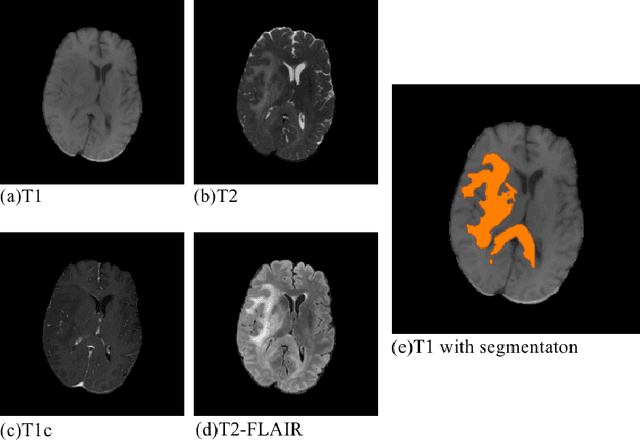

Convolutional neural networks (CNNs) have recently achieved remarkable success in automatically identifying organs or lesions on 3D medical images. Meanwhile, vision transformer networks have exhibited exceptional performance in 2D image classification tasks. Compared with CNNs, transformer networks have an obvious advantage of extracting long-range features due to their self-attention algorithm. Therefore, in this paper we present a CNN-Transformer combined model called BiTr-Unet for brain tumor segmentation on multi-modal MRI scans. The proposed BiTr-Unet achieves good performance on the BraTS 2021 validation dataset with mean Dice score 0.9076, 0.8392 and 0.8231, and mean Hausdorff distance 4.5322, 13.4592 and 14.9963 for the whole tumor, tumor core, and enhancing tumor, respectively.